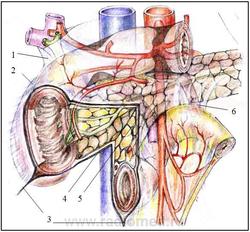

Рисунок 2.3. Хирургическая анатомия связочного аппарата двенадцатиперстной кишки.

1 - печеночно-двенадцатиперстная связка

2 - двенадцатиперстно-почечная связка

3 – собственная связка нижнегоризонтальной ветви ДПК

4 - позадипанкреатическая фасция

5 - предпанкреатические фасции

6 - связка Трейтца

Печеночно-двенадцатиперстная связка (рис. 2.3) наиболее крупная связка ДПК, которая не только поддерживает ее луковицу, верхний изгиб и нисходящую часть, но вместе с поджелудочной железой и остальные части ДПК. По своему происхождению она представляет собой часть вентральной брыжейки ДПК, расположенной между воротами печени, ДПК и поджелудочной железой и включает важнейшие анатомические структуры ДПК – желчный, панкреатический протоки и магистральные сосуды.

Двенадцатиперстно-почечная связка (рис. 2.3) представляет собой широкую горизонтальную желобообразную складку брюшины. Она расположена между наружным краем ДПК и областью ворот или нижней половины правой почки и вверху ограничивает сальниковое отверстие. В зоне двенадцатиперстно-почечной связки иногда врожденно формируются широкие фиброзные тяжи с выраженной сосудистой сетью, которые перекидываются через ДПК под бульбодуоденальным сфинктером, сдавливая начало или всю нисходящую часть ДПК. Здесь формируется первый перегиб ДПК при гастробульбоптозе – зона постбульбарного стаза.

Дуоденоеюнальный переход удерживается в своем положении прочной вертикально расположенной связкой Трейтца (рис. 2.3). Эта связка содержит пучки гладких мышечных волокон, берущих начало из циркулярного мышечного слоя кишки в месте ее крутого перегиба. Связка направляется вверх и несколько вправо, позади поджелудочной железы, веерообразно расширяется и прикрепляется у устья верхней брыжеечной артерии, чревного ствола и левой ножки диафрагмы, вплетаясь в волокна покрывающего их листка предпозвоночной фасции. Анатомические варианты двенадцатиперстной кишки и связки Трейтца представлены на рисунке 2.4.